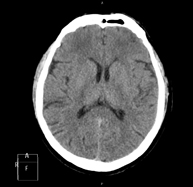

- TC Cráneo

Prueba radiológica que consiste en obtener imágenes del cráneo de alta definición anatómica (tronco cerebral, cerebelo, cerebro, calota craneal, etc.), mediante el empleo de un equipo de TC (Tomografía Computarizada).Indicaciones: traumatismos, cefalea, trastornos de la memoria, pérdida de fuerza súbita en una extremidad o mitad del cuerpo.

Prueba radiológica que consiste en obtener imágenes del cráneo de alta definición anatómica mediante el empleo de un equipo de TC (Tomografía Computarizada). Indicaciones: cefalea, estudio de tumores, traumatismo craneal.